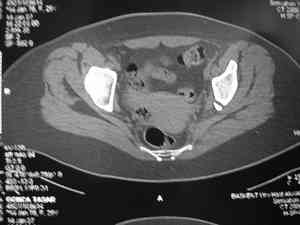

Dear group, 30 years age female MVA front seat, head trauma + post column left acetabular fracture, 2.5 weeks skeletal traction. She is now conscious but still confused without any surgical treatment for brain edema.

Latest X rays and CAT is attached. Fracture within first 1.5 cm from the weight bearing dome, although AP and Obtrator oblique good, iliac oblique view reveals some displacement. I'm not sure that nonsurgical treatment will be OK Hüseyin Demirors Baskent University Dept of Orthopedics and Travmatology Ankara TURKEY